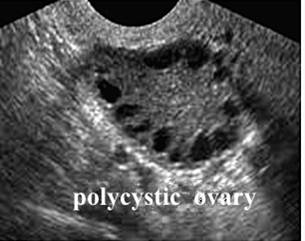

2.超声检查 见卵巢增大,包膜回声增强,轮廓较光滑,间质回声增强;一侧或两侧卵巢各有12个及以上直径为2~9mm无回声区,围绕卵巢边缘,呈车轮状排列,称为“项链征"(图29-7)。连续监测未见主导卵泡发育及排卵迹象。

图29-7 PCOS的超声图像(项链征)